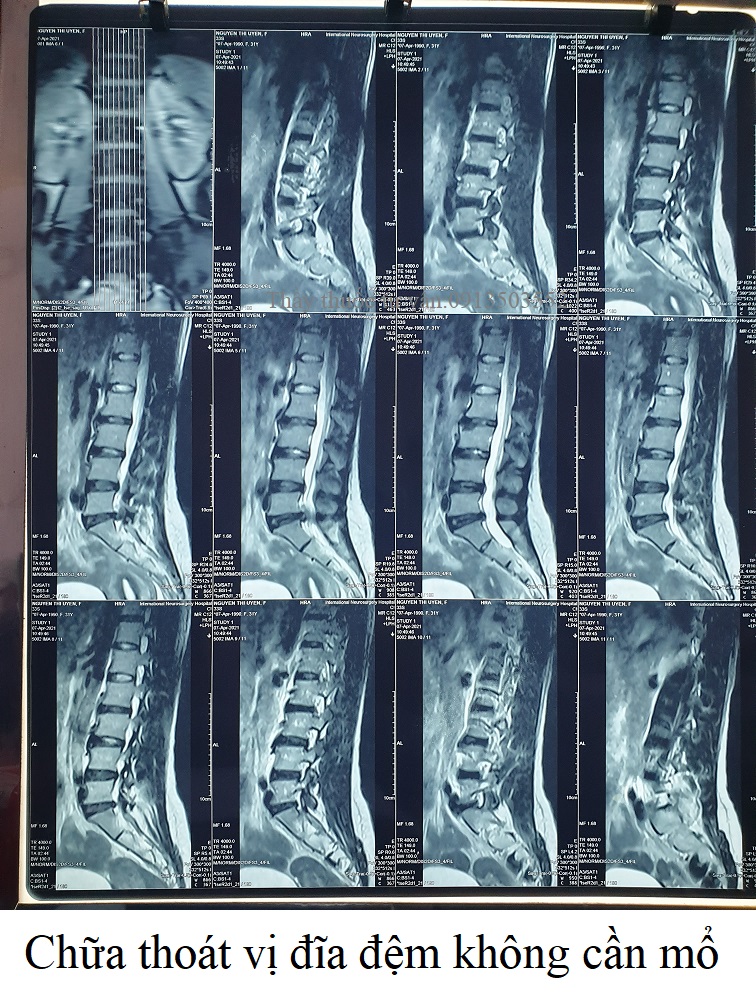

Chữa thoát vị đĩa đệm không cần mổ

Thầy thuốc đông y Nguyễn Văn Minh, phụ trách phòng khám đông y Bảo Minh ở TP.HCM. Ông đã chữa khỏi thoát vị đĩa đệm cho rất nhiều người, giúp họ không cần mổ thoát vị đĩa đệm. Khi khám bệnh cho họ, ông căn cứ vào kết quả chụp cộng hưởng từ cột sống để kê đơn thuốc phù hợp nhất, tốt nhất theo cơ địa và mức độ bệnh của họ nên tỉ lệ chữa khỏi bệnh luôn ở mức cao.❮ đọc tiếp ❯ -

Chụp MRI là cách phát hiện thoát vị đĩa đệm cột sống chính xác nhất

Đau cột sống lưng, cột sống cổ, tê bì chân tay....coi chừng bạn bị thoát vị đĩa đệm cột sống. Cách phát hiện và chẩn đoán hiệu quả nhất căn bệnh thoát vị đĩa đệm chính là chụp MRI cột sống (chụp cộng hưởng từ).❮ đọc tiếp ❯ -